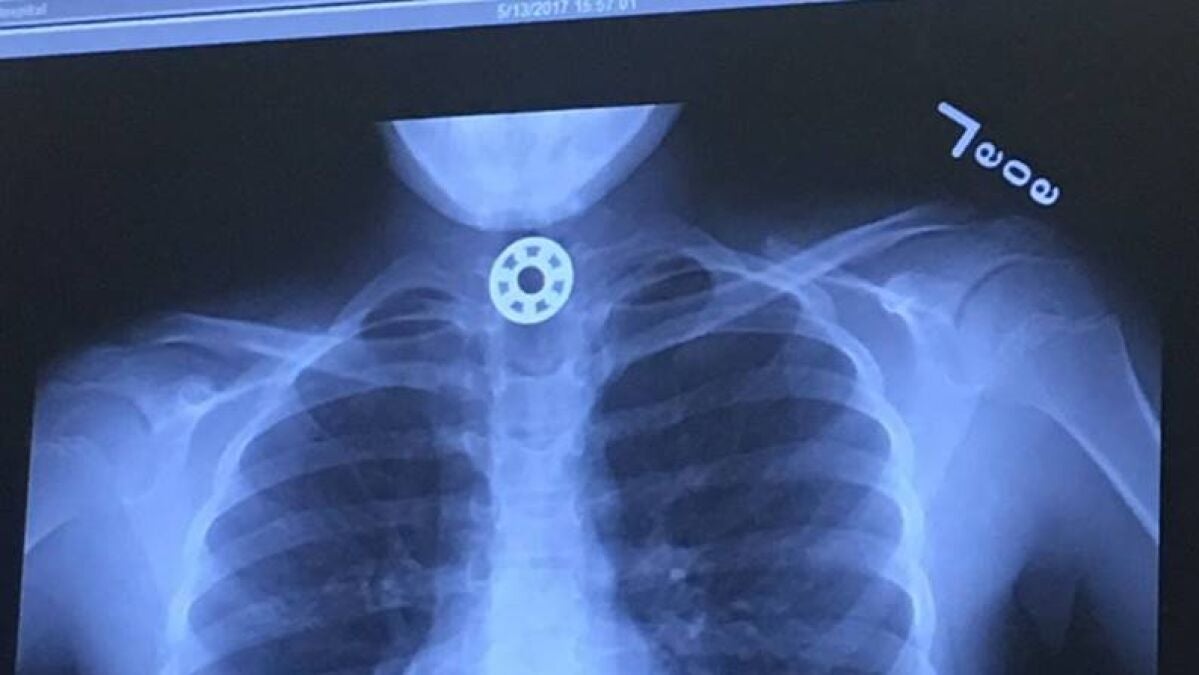

La niña se puso el Fidget Spinner en la boca para limpiarlo, pero sin darse cuenta se tragó una pieza. Tras esto comenzó a ponerse roja y a hacer ruidos para alertar a su madre, que rápidamente la llevó al hospital, donde gracias a una radiografía vieron el juguete atascado en su esófago.

La madre, angustiada, trató de recibir ayuda médica rápidamente, pero los doctores no eran capaces de identificar dónde estaba el extraño objeto que la niña se había tragado. La pequeña fue trasladada al Hospital Infantil de Texas para que le realizaran una radiografía que mostró el juguete alojado en su esófago.